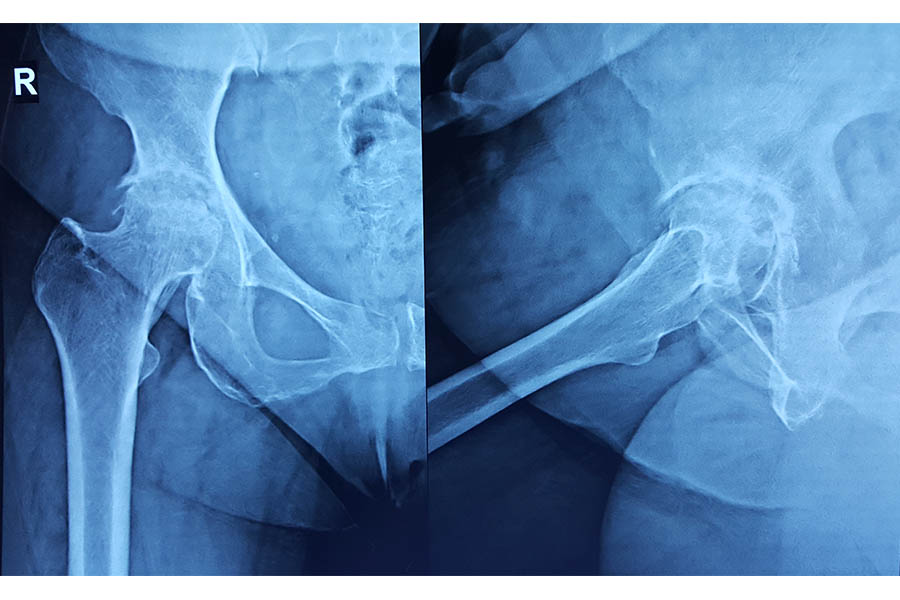

Difficult Replacement

Case 1